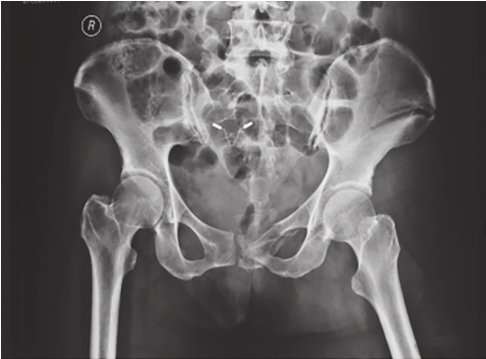

最为常用,患者仰卧,射线呈前后方向垂直投射,骨盆入口边缘与躯干纵轴呈45°~60°夹角。该位像基本能了解骨盆前后环骨折及骶髂关节骨折脱位情况。可用于鉴别骶骨、骨盆髋臼、近端股骨等部位骨折(图2-1)。

图2-1 骨盆前后位X线片

可见左侧骶髂关节骶骨及髂骨面局部骨质断裂,关节间隙增宽,左侧耻上、下支骨折,累及耻骨联合左侧缘。